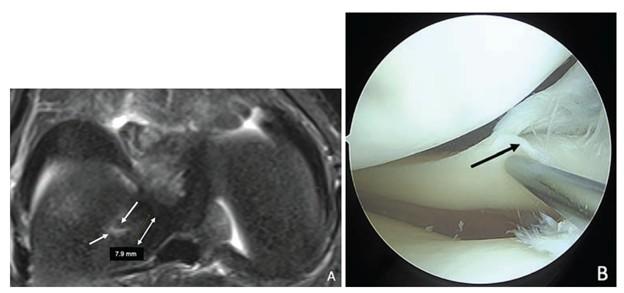

A and B, Axial T2-weighted fat-suppressed MR image (A) and corresponding arthroscopic image (B) in 15-year-old boy show LMORT Type 1 (incomplete tear) lesion (single-headed arrows). Double-headed arrow in A indicates measurement of tear extent from posterior root attachment. (Photo: American Journal of Roentgenology (AJR))

September 24, 2025—According to the American Journal of Roentgenology (AJR), MRI can reliably identify lateral meniscal oblique radial tears (LMORTs) — a biomechanically important tear pattern associated with anterior cruciate ligament (ACL) injury — using arthroscopy as the reference standard.

MRI demonstrated sensitivity of 76.5–80.4% and specificity of 54.9–88.2% for distinguishing LMORTs from other posterior lateral meniscal tears, with moderate to substantial interreader agreement (κ = 0.443–0.747). Sensitivity was highest for Type 3 and Type 4 lesions (82.6–91.3%), compared to Type 1 (12.5–25.0%) or Type 2 (0–27.3%) lesions. Lateral meniscal extrusion emerged as an independent predictor of LMORT presence (p = .049).